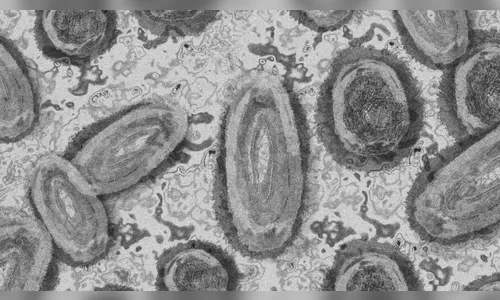

Autor A varíola dos macacos é uma doença viral rara transmitida pelo contato próximo com uma pessoa infectada e com lesões de pele - Foto: Pixabay

A varíola dos macacos, em inglês, monkeypox, é uma doença viral rara transmitida pelo contato próximo com uma pessoa infectada e com lesões de pele. O contato pode ser por abraço, beijo, massagens ou relações sexuais. A doença também é transmitida por secreções respiratórias.